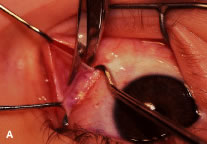

RECESSION PROCEDURE: LIMBAL APPROACH

Two 6-0 silk stay sutures are passed through the conjunctiva and superficial scleral tissue at the limbus (see Fig. 49). These sutures are used to stabilize the globe during the procedure. These stabilizing sutures attached to bulldog clamps will hold the globe in adduction or abduction as required.

A no. 15 surgical knife or other similar instrument is used to penetrate the conjunctiva at the limbus (Fig. 50). Care is taken to approach the limbustangential to the globe so that inadvertent penetration of the sclera or cornea is avoided. A Westcott scissors also may be used to incise the conjunctiva at the limbus. To facilitate this step, conjunctiva is lifted gently with a 0.5-mm Castroviejo forceps (see Fig. 50).

|

A blunt-tipped Westcott scissors is used to extend the incision for about 3 clock hours (Fig. 51). Once the fused area of conjunctiva and anterior Tenon's capsule has been penetrated, blunt dissection is performed to carry the limbal incision back toward the muscle. This maneuver is best accomplished by directing the closed tips of a blunt-tipped Westcott scissors into the tissue and letting them open to spread the tissue in a plane between the scleral surface and the underside of Tenon's tissue. The limbal incision is extended radially with a Westcott scissors (Fig. 52). Care is taken to avoid cutting into the anterior portion of the rectus muscle insertion (Fig. 53).

|

|

Figure 54 shows the conjunctiva being elevated by the assistant with Castroviejo forceps. The anterior extension of the muscle can be seen.

|

A Jameson hook is passed under the rectus muscle about 2 mm posterior to the insertion (Fig. 55). The insertion has been identified previously with a Stevens' hook that is used to lift up the tendon to facilitate passage of the Jameson hook.

Figure 56 shows sharp dissection of the intermuscular septa and the check ligaments that extend from the orbital surface of the muscle. The assistant applies gentle traction to the conjunctiva to show the surgeon the weblike bands that are to be cut. Care is taken not to penetrate the muscle capsule because penetration can injure the muscle and will cause bleeding. This dissection is carried back about 4 to 5 mm for recessions and 5 to 9 mm for resections.